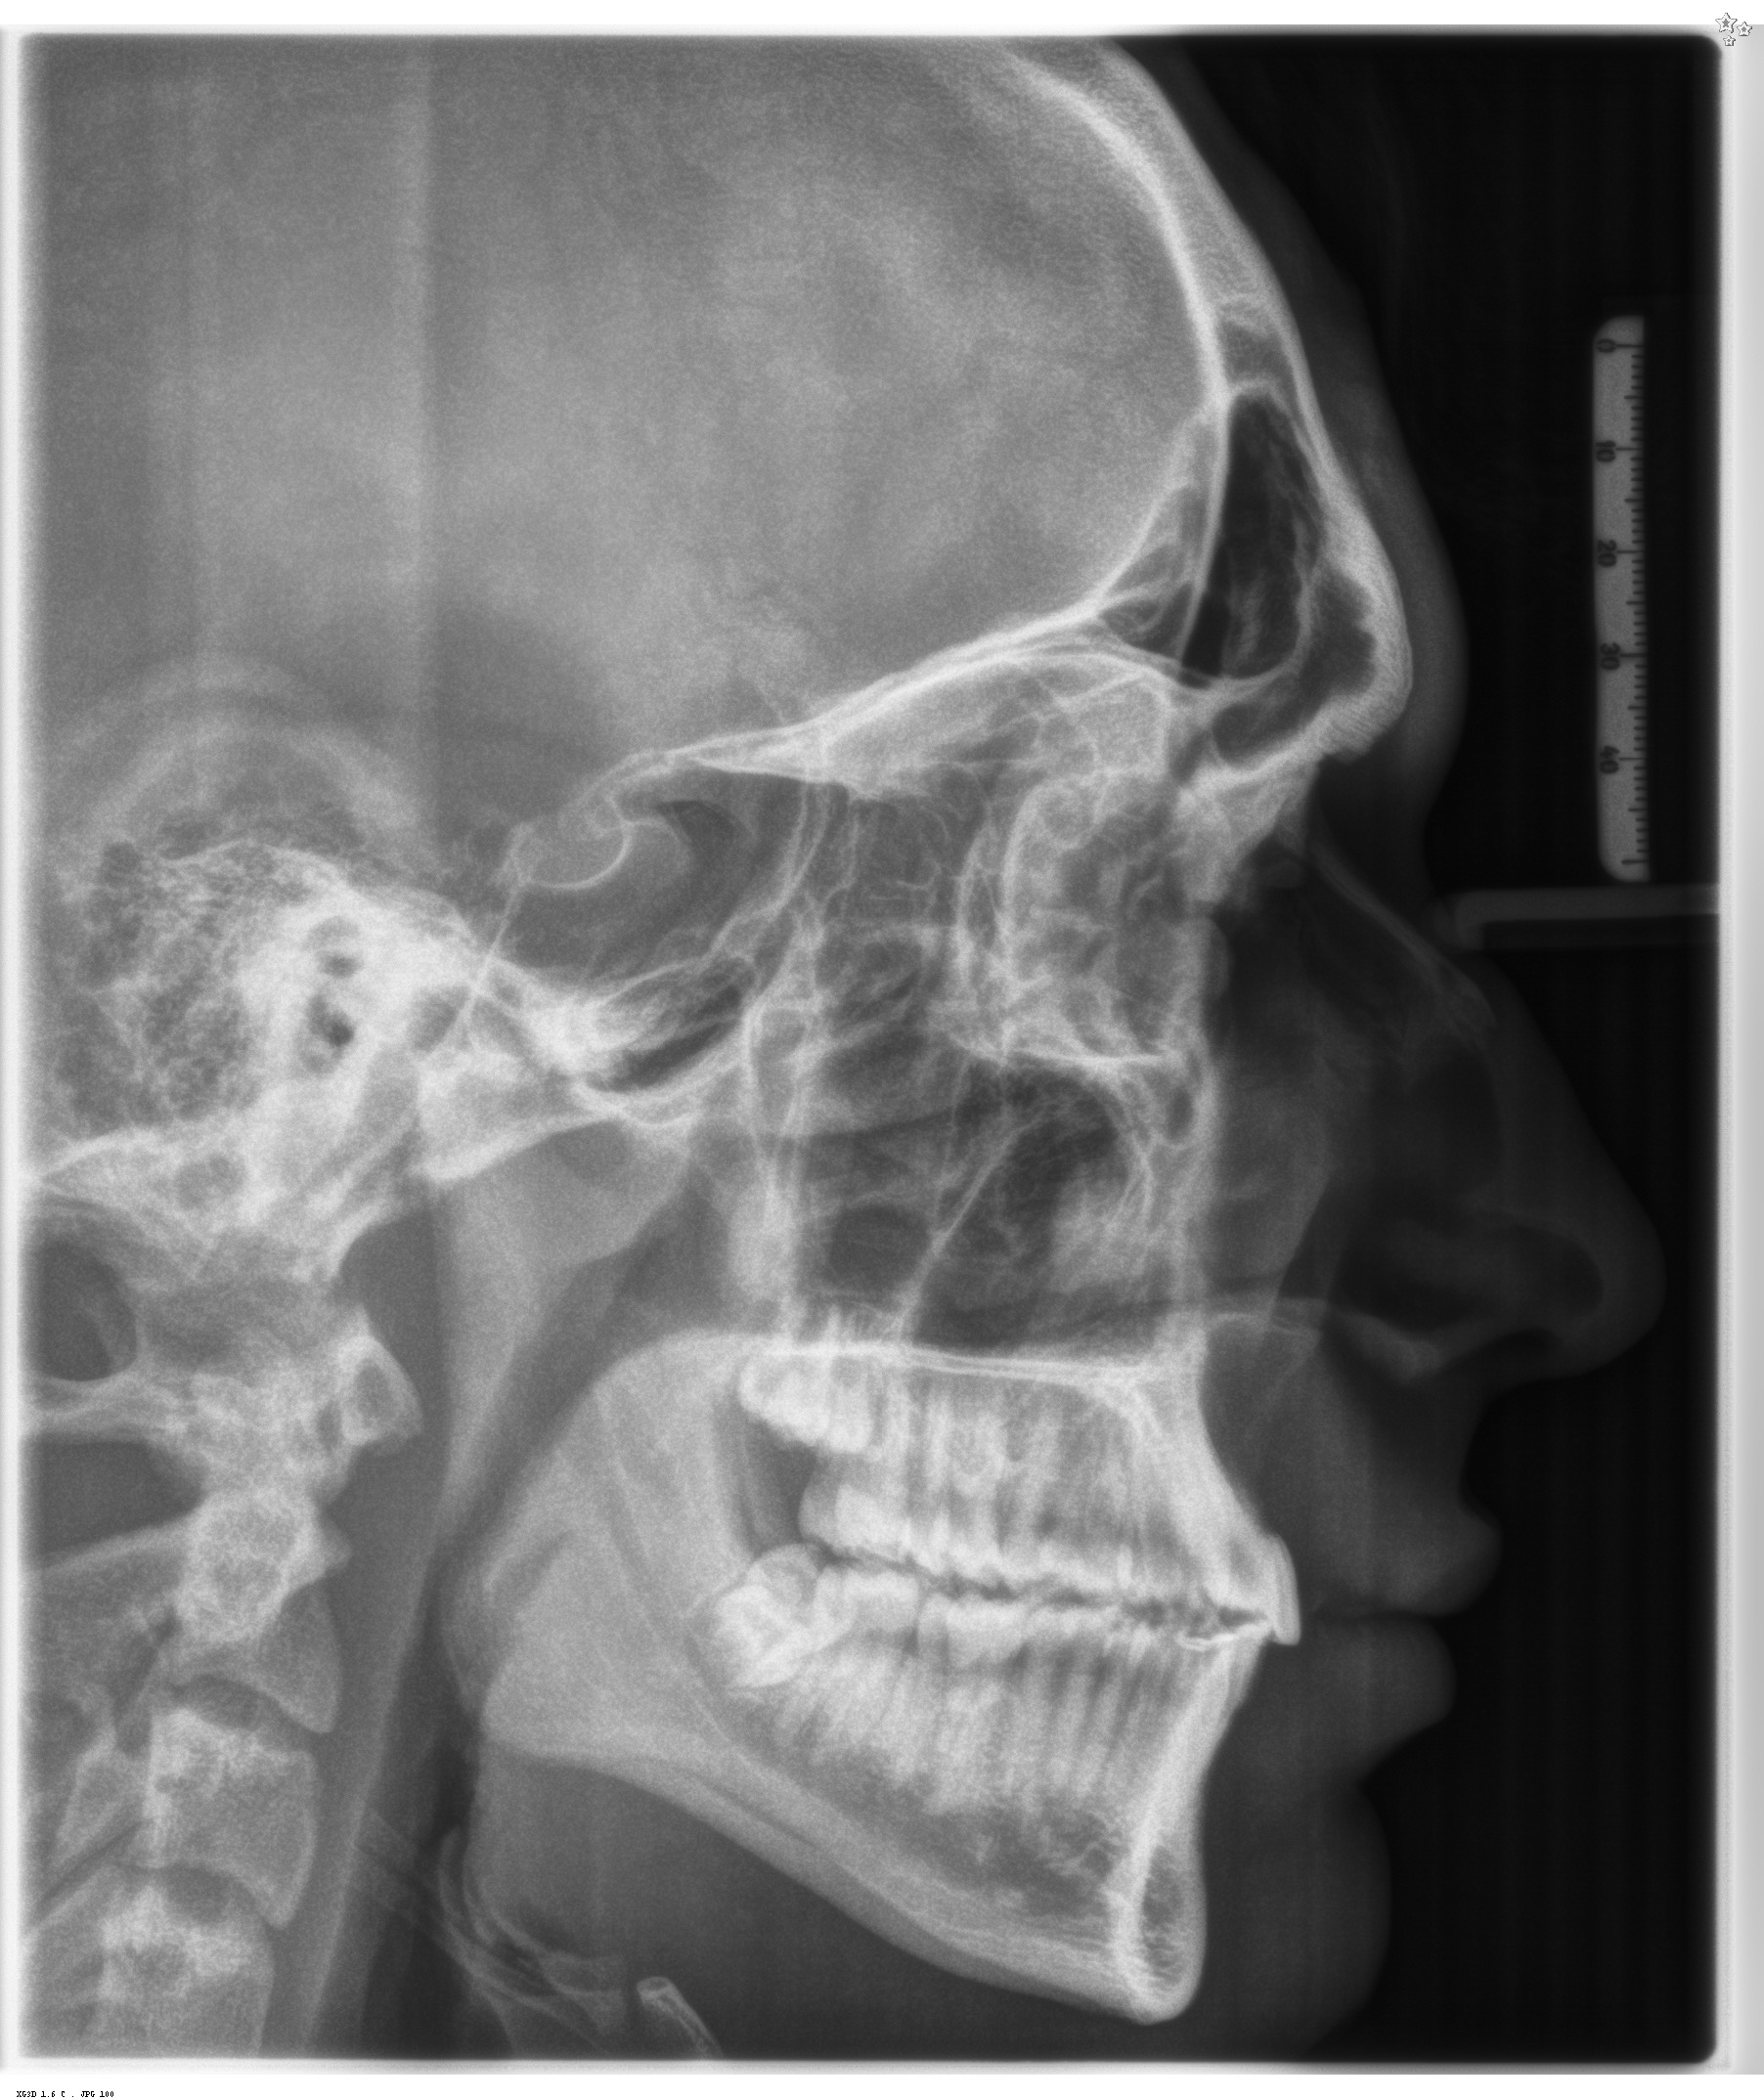

I’m attaching the X-ray I took a few weeks ago. Let me know what you guys think structurally and what approach you’d consider in my case.

I’m attaching the X-ray I took a few weeks ago. Let me know what you guys think structurally and what approach you’d consider in my case.